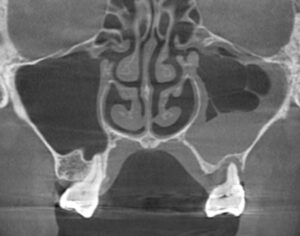

今回、左上の奥歯の違和感と鼻閉感(鼻声)を訴えられた患者様に対してCT撮影を行いました。

重度の歯周病になった左上奥歯の周囲の骨は大きく吸収し、左側の上顎洞には膿が溜まった状態でした。

右側の上顎洞の状態(正常な場合は空洞内全体が黒く写る)に比べて左側は白く濁っていましたが、左側の上顎洞の空気の通り道は細いながらも通じており、鼻が原因ではなく歯が原因の上顎洞炎であると診断しました。